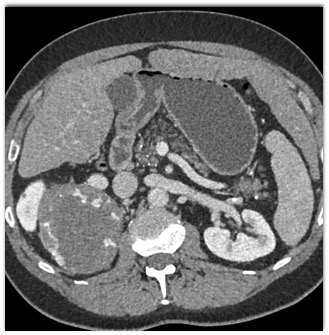

Based on CT findings the most likely diagnosis is?

pheochromocytoma

primary adrenal carcinoma

metastatic melanoma

adrenal cortical adenoma